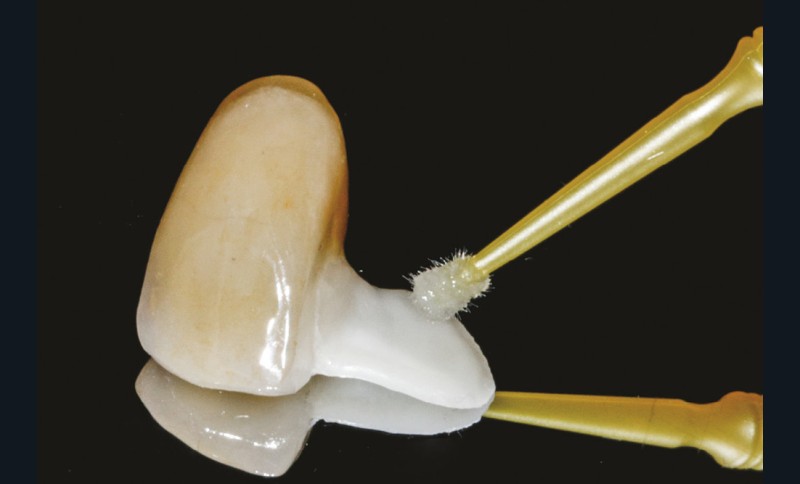

Le Clearfil Ceramic Primer (Kuraray Noritake) est appliqué sur la pièce prothétique pendant 20 secondes puis séché modérément (fig. 21). Une fois le champ opératoire (Nictone, MDC Dental) mis en place (fig. 22), le conditionnement tissulaire de la 11 se fait par mordançage à l’acide orthophosphorique 40 %, rinçage et séchage. Le Panavia V5 Tooth Primer (Kuraray Noritake) est ensuite appliqué sur la dent pendant 20 secondes, puis séché (fig. 23 et 24).